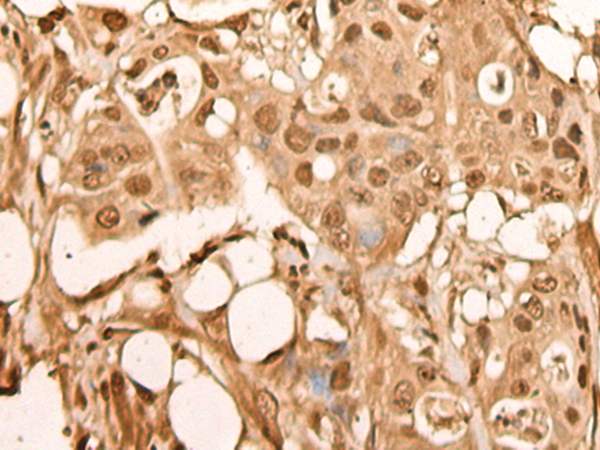

IHC (Immunohistochemistry)

(The image on the left is immunohistochemistry of paraffin-embedded Human liver cancer tissue using 46356(BRF2 Antibody) at dilution 1/40, on the right is treated with fusion protein. (Original magnification: x200))